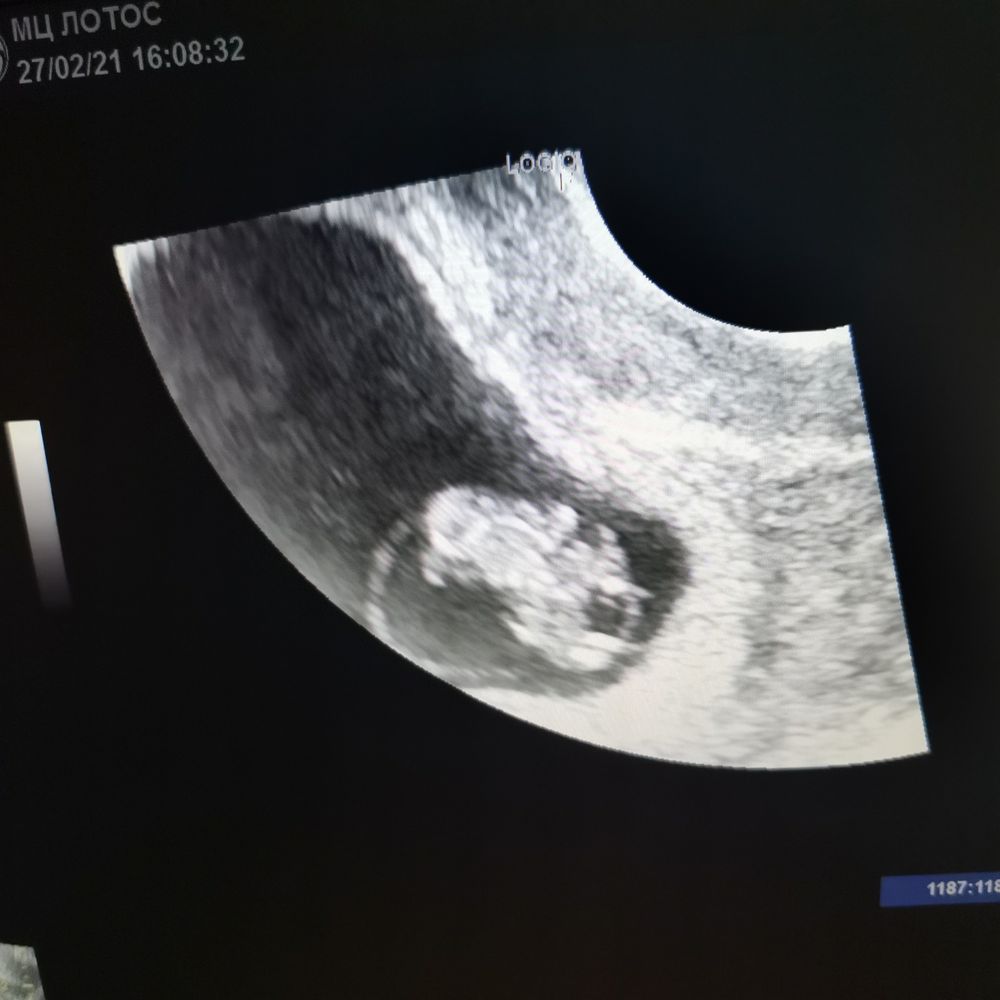

Беременность- 1 триместр ( только до 10 недель)Что там метод Рамзи говорит? Кто там разбирается?

Девочка